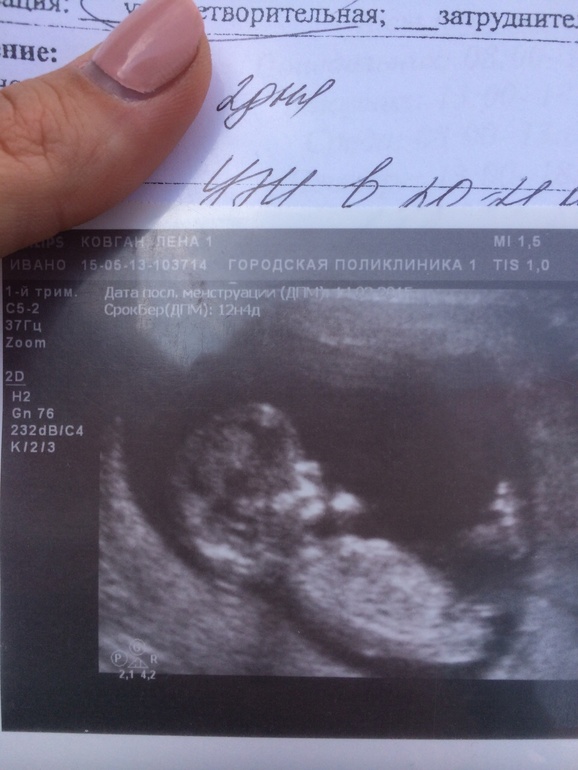

Приветик)) Сегодня прошла первый скрининг, все хорошо тьфу тьфу по УЗИ, кровь ещё не пришла, ждёмс, но я уверена, что там тоже всё тип топ)) Доктор по половому бугорку предположила, что будет девочка, прям как я мечтала ❤️ Но предупредил, что 100% гарантии нет, так как срок ещё мал. Девочки, посмотрите наш половой бугорок и сравните с вашими! Вот у кого нибудь примерно с таким же родился в итоге парень?))

У вас кажется девочка) нам на первом скрининге сказали и так дальше только подтверждали. Фото нашего бугорка на руки не дали но я помню что вот такой ракурс как у вас был на мониторе, и бугорочек торчал вверх... а у вас он лежит как бы).

Мне на скрининге даже предполагать не стали. Но я увидела такой же бугорок. Сама девочку предположила. Уже 3 раза подтвердили девочку.